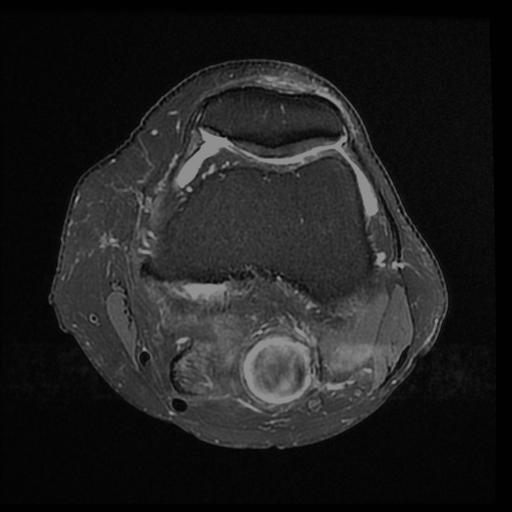

Popliteal Artery Aneurism